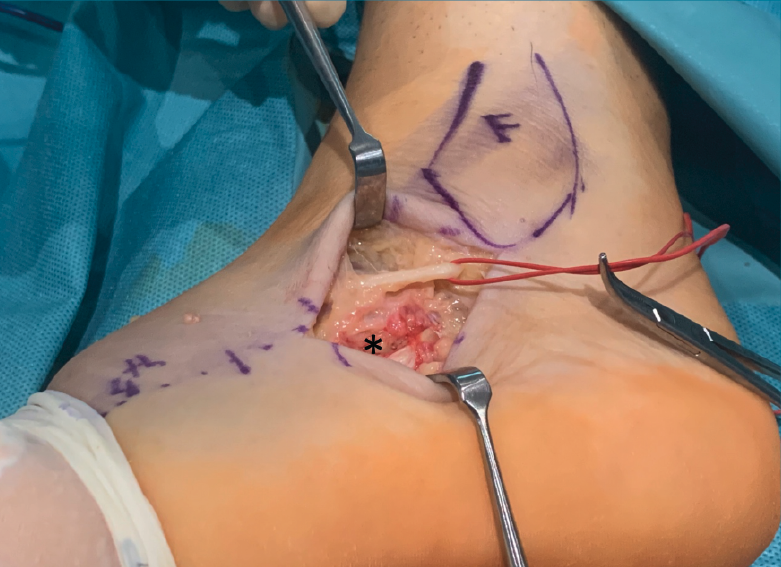

Figura 2. Trayecto del nervio sural (con vessel loop) y de los tendones peroneos (*) en riesgo durante el abordaje.

Para realizar el abordaje del seno del tarso(13) se sigue una línea imaginaria que discurre desde el eje del cuarto metatarsiano hasta la punta del maléolo lateral, realizando una la incisión de 2-3 cm sobre esta línea (se puede ampliar la incisión tanto hacia proximal como a distal) (Figura 1). La disección se debe realizar con cuidado para no dañar el nervio sural ni a los tendones peroneos que cruzan la incisión (Figura 2). Finalmente, se debe abrir el ligamento peroneo-calcáneo para acceder a la articulación subastragalina posterior; este paso no ha demostrado provocar inestabilidad de tobillo durante la evolución posterior.